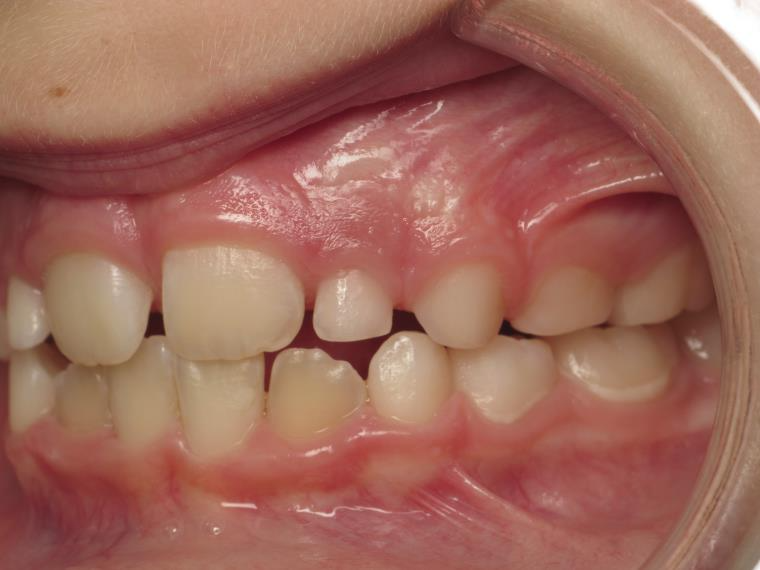

appareillage mobile

bilan début fin de traitement